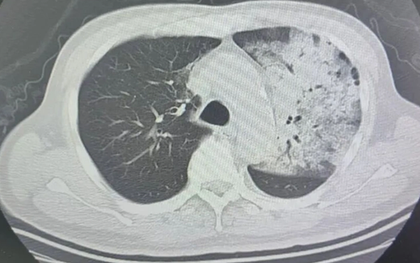

Người đàn ông sốt 40 độ C, phổi gần như "trắng xóa", chỉ vài ngày đã suy đa tạng: Thủ phạm liên quan đến thói quen nhiều gia đình vẫn mắc

Một chiếc điều hòa lâu ngày không được vệ sinh có thể tiềm ẩn rủi ro sức khỏe nghiêm trọng mà nhiều người không ngờ tới.